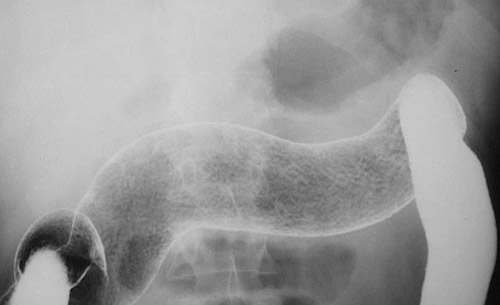

This barium enema demonstrates a close view of a granular area of the mucosa involving the transverse colon. The course of ulcerative colitis can be marked by exacerbations and remissions, just like Crohn's disease.